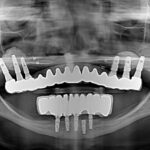

Dr. Omid Termechi is a distinguished dental professional specializing in implant dentistry, with a strong reputation as a practitioner, educator, and innovator in the field. Operating primarily out of his office located at 30-12 30th Avenue, Suite 230, Astoria, NY, Dr. Termechi has established himself as a trusted provider of...

Dr. Abdulla S. Zoobi, DDS, is a highly skilled and experienced oral and maxillofacial surgeon and dentist based in Astoria, New York. With a Doctor of Dental Surgery degree from the State University of New York at Stony Brook Dental School, Dr. Zoobi has dedicated his career to providing comprehensive...

Elements Dental of NY, located at 28-36 Steinway Street in the heart of Astoria, NY 11103, stands as a premier dental practice dedicated to transforming smiles through advanced dental implant solutions and comprehensive oral care. Under the expert guidance of Dr. Abdulla Zoobi, DDS, this state-of-the-art clinic has established itself...

New York Dental Astoria, founded and led by Dr. Aristides Rotsos, DMD (also known as Dr. Ari Rotsos), stands as a premier destination for advanced cosmetic, implant, and general dentistry in the heart of Astoria, Queens, New York. Established in January 2003, this state-of-the-art practice has flourished for over 20...